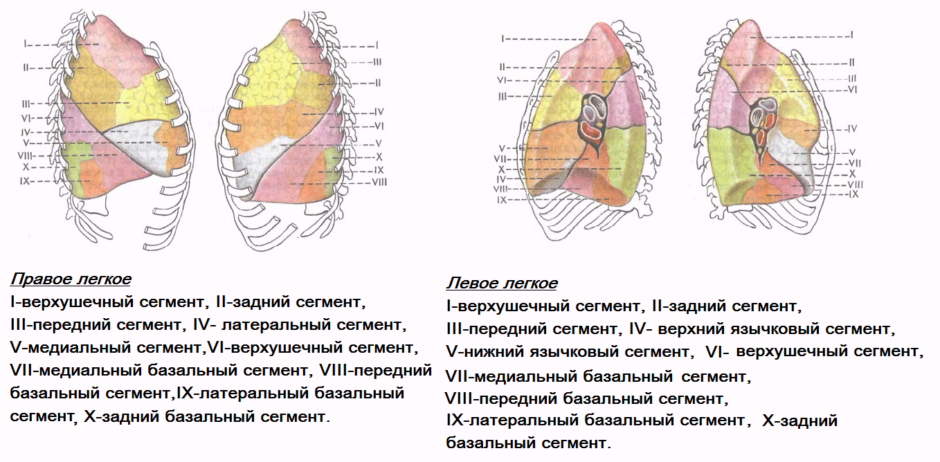

Анатомические изображения сегментов легких различных животных

Раздел: Другие животные